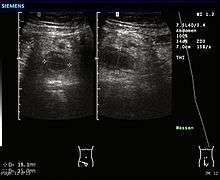

Ultrasound image of acute appendicitis

Ultrasonography and Doppler sonography are useful to detect appendicitis, especially in children. Ultrasound can show free fluid collection in the right iliac fossa, along with a visible appendix with increased blood flow when using color Doppler, and noncompressibility of the appendix, as it is essentially a walled off abscess. Other secondary sonographic signs of acute appendicitis include the presence of echogenic mesenteric fat surrounding the appendix and the acoustic shadowing of an appendicolith.[45] In some cases (approximately 5%),[46] ultrasonography of the iliac fossa does not reveal any abnormalities despite the presence of appendicitis. This false negative finding is especially true of early appendicitis before the appendix has become significantly distended. In addition, false negative findings are more common in adults where larger amounts of fat and bowel gas make visualizing the appendix technically difficult. Despite these limitations, sonographic imaging in experienced hands can often distinguish between appendicitis and other diseases with similar symptoms. Some of these conditions include inflammation of lymph nodes near the appendix or pain originating from other pelvic organs such as the ovaries or Fallopian tubes.